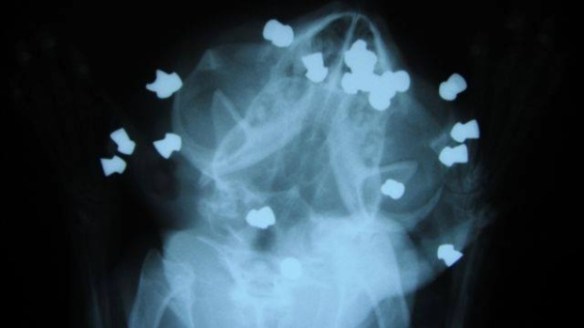

Joe is by definition a true survivor, some might even call him a miracle cat. In February of 2014 he was found by the side of the road in Sarnia Ontario, where he had been left for dead, he had been shot in the head 17 times with a pellet gun. A good Samaritan saw Joe, picked him up and brought him to the The Sarnia and District Humane Society where he was later transferred to the Blue Cross Animal Hospital to receive treatment.

Joe’s x-ray after the shooting shows the pellets lodged in his head – source CBC news

Joe, who underwent multiple surgeries, lost an eye but had a good overall recovery from his wounds thanks to the animal organizations involved. People in the community and from around the world came to his support raising $33,000 for the Sarnia and District Humane Society, more than enough to cover Joe’s medical care. The remaining donations will be used to pay medical bills for other rescue animals through the shelters Wanda’s Wish fund. Joe’s case has also helped bring much-needed attention to the common and horrible crime of animal abuse. His story has galvanized a community to speak out for stronger penalties and tougher animal cruelty laws in Canada, which most can agree are currently way to lenient.